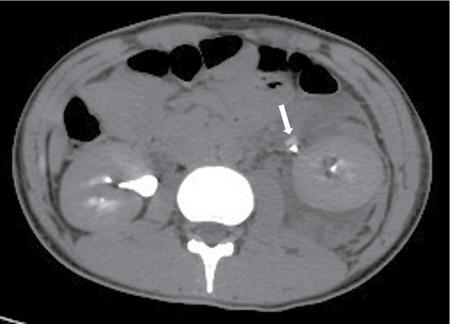

Management of renal and genitourinary trauma has evolved during the last decades. There has been a transition towards conservative nonoperative management. This is due to the safety and outcome of the nonoperative approach in patients with renal trauma as well as in those with injury to other organs such as the liver and spleen. Improvement in imaging technique and minimally invasive treatment have also led to this. Techniques such as angioembolization in case of active bleeding and stenting in cases of urine extravasation have helped. FAST (focused assessment with sonography in trauma) plays a limited, though critical role as it evaluates presence of fluid presumed to be hemoperitoneum, on an abdominal ultrasound. This is important as ultrasound is easily available and inexpensive. In the presence of fluid, a stable patient undergoes CT abdomen. It is important to clamp the urinary bladder catheter if introduced prior to the scan, to partially distend the bladder so that it may be evaluated on US/CT. Contrast-Enhanced Multi-Detector Computed Tomography (MDCT) is the gold standard for imaging patients with blunt or penetrating abdominal injury who are hemodynamically stable. It rapidly completely evaluates both the upper and lower urinary tract. It also permits diagnosis of injury to other viscera, hence determining further patient management. Urethrography and cystography are useful for specific evaluation of urethral and bladder injuries. Protocol for the CT scan would include a non-contrast scan. In an acute setting no oral or rectal contrast can be administered. The protocol to be followed is a three-phase study – obtained in arterial, portal and venous phases followed by a delayed phase. Intravenous Pyelogram: In the era of CT, intravenous pyelogram has limited role in detection of renal injuries. Since its sensitivity is less, it should be done only when CT is not available. One-shot intravenous urography should be considered in hemodynamically unstable patients taken to the operating room for renal exploration or nephrectomy without prior imaging. In one-shot intravenous urography, 2 mL/kg contrast is injected and a delayed film of KUB region is obtained after 10–15 minutes to check for functioning contralateral kidney. Magnetic Resonance Imaging: Although CT and MRI are equally effective in staging the renal injuries, use of MRI is limited because of longer scan time, increased cost, and uncooperative patients in acute trauma setting. MRI can be an alternative to CT in patients allergic to iodinated contrast and pregnant patients. Retrograde Pyelography is very sensitive technique for detection of renal pelvis and ureter injuries. It is often used to outline the extent of renal pelvis and ureteric injury detected on CT or intravenous urography if additional clinical information is required. Its main advantage is it permits simultaneous placement of a ureteral stent if required. Radionuclide Renal Scintigraphy plays limited role in renal trauma. It is indicated to document function of kidney in patients with contraindication to iodine-based contrast or following up of repair of renovascular trauma. Commonly used radiopharmaceuticals in the renal scintigraphy are technetium 99m glucoheptonate, technetium 99m mercaptoacetyltriglycine, or technetium 99m diethylenetriamine pentacetic acid. Kidneys are third most commonly injured organ after blunt trauma. It is most commonly injured organ of genitourinary system and accounts for approximately 8%–10% of the abdominal injuries. The incidence of kidney injury in genitourinary trauma is 65%–90%. Males are three time more prone to injuries than female. In a large number of cases, renal trauma is isolated, however, 80%–95% of patients have other associated injuries. The kidneys are relatively well protected in the retroperitoneum, covered by fat and the Gerota’s fascia; however, despite this they are the most commonly injured organ of the urinary system. In a patient with history of trauma imaging is advised whenever there is abdominal tenderness, guarding, or rigidity. In institutes with dedicated trauma care centres, usually, all the patients with history of abdominal trauma undergo initial ultrasound evaluation (FAST). Hemodynamically stable patients found to have abdominal free fluid or hemoperitoneum on FAST further undergo dedicated cross-sectional imaging. All the trauma patients admitted to the hospital should be first evaluated for life-threatening injury with the advanced trauma life support approach. Then a survey should be done to look for flank tenderness, ecchymosis, and laceration, which may indicate renal injury. There are no consistent clinical features of renal injury and hence its clinical diagnosis is difficult to make. The best indicator of significant urinary system injury is macroscopic and microscopic haematuria but degree of haematuria does not match with the grade of injury. Minor injuries can produce macroscopic haematuria. Major injuries may not produce haematuria. Haematuria is absent in 50% of grade II injury, 7% of grade IV injury, 36% of renal vascular injury and 50% of ureteropelvic junction injury. Hence clinicians should not depend only on presence or absence of haematuria in the assessment of a patient with suspected renal trauma. Significant blow to the flank, especially acceleration and deceleration injury, ecchymosis of the flank, presence of entry and exit wounds in the flank, fracture of the lower ribs and dorso-lumbar vertebrae, hypotension with microscopic haematuria, macroscopic haematuria and presence of associated major injuries should make the clinician alert of renal injury and warrants immediate imaging assessment. Kidneys are well secured intraabdominal organ. Its high location in the retroperitoneum, surrounding fat and fascia, and neighbouring muscles, vertebrae and overlying ribs provide protection to the kidney. In children and adolescent, kidneys are more vulnerable to damage in abdominal injury because it is more inferiorly present in the abdomen, its larger size relative to the abdominal cavity, weaker connective tissue and fascia, less developed abdominal and paraspinal muscles, less ossification of lower ribs, and more mobility on its vascular pedicle. Understanding the mechanism of injury is important, because if a history of high acceleration and deceleration forces is elicited, the likelihood of renal injury is high and the patient should undergo imaging. The major elements causing renal trauma are the acceleration-deceleration forces. These cause injury to the renal pedicle and the ureteropelvic junction with resultant rupture or thrombosis. Acceleration forces may cause collision of the kidney with the surrounding ribs and spine. This results in parenchymal and vascular injury. Penetrating trauma causes greater damage due to the large amount of energy which is transmitted to the tissues. This causes cavitation, creating shear forces when the cavity collapses resulting in destruction in a larger area than just the urinary tract. There is tissue disruption, rupture of blood vessels and nerves and associated fractures. Most common mechanism of injury is blunt trauma and accounts for 80%–90% of cases. It is caused by motor vehicle accident, fall, sport, assault and pedestrian accident. Major factors that contributes to renal injury in blunt trauma are acceleration and deceleration forces. These forces result in shear injury. Kidneys are freely floating organ in the surrounding fat and fixed only at renal hilum and ureteropelvic junction. Hence it is more vulnerable to acceleration and deceleration injuries that rapidly and forcibly dislocate the kidneys. Rapid deceleration causes relative foreword movement of the kidney against a fixed hilum. It produces tension on the renal pedicle that lead to vascular laceration, thrombosis and ureteropelvic junction disruption. Rapid acceleration causes collision of kidney against the surrounding ribs and spine. It produces renal parenchymal and vascular injury. If the patient has past history of existing renal disease further imaging studies are indicated. In case of a solitary kidney or solitary functioning kidney, it is important to preserve the kidney even if it is damaged. Penetrating injury accounts for 10%–20% of cases. It is caused by gunshot and stab wounds. Most injuries are more severe and less predictable than blunt trauma. They are classified as high velocity, medium velocity, and low-velocity injuries. In high-velocity injuries, the damage usually extends beyond the path of projectile. The bullet conducts large amounts of energy to the tissues that creates a transient expansive cavitation in the tissue around the tract. This cavitation immediately collapses and built shear forces that causes tissue damage, injury to the blood vessels, nerves and bones in a much larger area than the projectile tract itself. In low-velocity injuries, the damage is usually limited to the path of the projectile. Entry site in the flank, upper abdomen and lower chest should alert the clinician and the radiologist to possible renal injury. Trauma through the anterior axillary line is commonly associated with injury to renal pelvis and vascular pedicle while trauma through the posterior axillary line causes damage to the renal parenchyma. Rarely kidneys can be exposed to iatrogenic injuries. It takes place during abdominal surgeries, percutaneous needle biopsy, percutaneous nephrostomy and extracorporeal shock wave lithotripsy. Kidneys with congenital and acquired conditions like ectopic location, PUJ obstruction, hydronephrosis, cysts and tumours are more vulnerable to blunt low velocity impact. Pathological kidney is less anatomically protected from the nearby structures. Furthermore, urine containing hydronephrotic kidney increases the force applied, worsening the severity of injury. Purpose of imaging are to detect renal injury, to assess the extent of organ damage and classify it, to demonstrate preexisting renal abnormalities, and to detect injuries of other organs. Criteria for imaging are: Children often do not show signs of hypotension despite significant blood loss but can still have significant renal injury. After trauma, they have high catecholamine output which maintains blood pressure until approximately 50% of blood volume has been lost. Hence liberal use of imaging is warranted in children. Organ Injury Scale (OIS) by American Association for the surgery of trauma (AAST) is most widely used trauma injury grading system. It was originally established in 1989. The original grading system did not fully consider vascular injury in its classification. Hence, it was revised in 2015 and published in 2018 (Table 10.12.5.2.1 and Graphic 10.12.5.2.1). It provides five grades of injury. Grade I–III represents low-grade injuries while grade IV–V represents high-grade injuries. Grade I injury accounts for 22%–28% of cases. It is characterized by renal parenchymal contusions and subcapsular haematoma. Contusions may be hypoechoic, hyperechoic or heterogeneous on sonography. It is seen as an ill-defined hypoechoic area with reduced perfusion on contrast-enhanced sonography. It may appear iso-dense or sometime hyperdense to normal renal parenchyma depending on the presence of clotted blood on plain CT images. Its detection is limited on the corticomedullary phase due to suboptimal enhancement of renal pyramids. It is characterized by focal ill-defined area of decreased enhancement on nephrographic phase. Excretory phase shows delayed or striated nephrogram of increased enhancement due to retained parenchymal contrast. A contusion must be differentiated from renal infarct, which would upgrade the renal injury. Contusion is ill-defined with enhancement on delayed images while infarct is typically wedge-shaped with no enhancement on delayed images. Subcapsular haematoma is well defined haemorrhagic collection along the renal surface between the renal capsule and parenchyma. It is seen as a non-enhancing lenticular area around renal parenchyma on contrast-enhanced ultrasound. Its density depends on the stage of blood. Acute haematoma typically appears hyperdense relative to renal parenchyma on plain CT images and does not show enhancement on post contrast images. As chronicity increases, its density decreases. Small haematoma is crescentic and large haematoma is biconvex. It causes mass effect on the underlying renal parenchyma, deforms the surface but does no displace the kidney. Occasionally, it causes enough pressure to decrease the renal perfusion and results in reactive hypertension, the so-called page kidney. Sometime, pseudosubcapsular haematoma may appear as hypodense collection along the renal surface. It is caused by patient movement during data acquisition. Presence of similar artifact in the other region on the same image helps to differentiate between true subcapsular haematoma and pseudosubcapsular haematoma. Pseudofracture appears as a sharp indentation of the renal contour near the renal hilum. It is seen on axial CT images at the level of hilar lobulation. Its characteristic location and absence of the perirenal fluid are clues to the correct diagnosis. Grade II injury accounts for 28%–30% of cases. It is characterized by renal parenchymal laceration ≤1 cm in depth without involvement of collecting system and perirenal haematoma limited by Gerota fascia. On contrast-enhanced ultrasound, renal lacerations are seen as linear or branching hypoechoic bands perpendicular to the capsule and may be associated with capsular discontinuity. They appear as irregular, linear or branching hypodense clefts extending from the renal capsule in the parenchyma on CT. Lacerations generally contains clotted blood and hence do not enhance on post contrast images. They are visualized on portal venous phase. Perinephric haematoma is collection present between the renal capsule and Gerota fascia. Because it is contained in the Gerota fascia it produces tamponade effect on renal bleeding. Acute haematoma typically appears hyperdense relative to renal parenchyma on plain CT images and does not show enhancement on post contrast images. It extends over a wider area and generally displaces the kidney rather than causing focal indentation on the renal surface. Rarely, localized perinephric haematoma limited to the renal capsule and bridging septum can produce focal indentation of the renal surface and mimics like subcapsular haematoma. Perinephric haematoma can occur as an isolated injury, but it is often associated with renal and/or vascular injury. Hence presence of perinephric haematoma should make the radiologist alert to look for associated injuries. Occasionally, it crosses the midline and spreads in the pelvis while still being limited by Gerota fascia. Presence of fluid in this region may be medial extension of perinephric haematoma in grade II injury, haemorrhage from renal vascular damage in grade III injury, or extravasated urine in grade IV injury. Hence, medially present collections should be more carefully evaluated. Grade III injury (Fig. 10.12.5.2.1) accounts for 22%–26% of cases. It is characterized by renal parenchymal laceration >1 cm in depth without involvement of collecting system and any low-grade trauma with associated vascular injury or active bleeding limited by Gerota fascia. Laceration involves the renal cortex and medulla. When deep lacerations are present, it is important to check the status of pelvicalyceal system. Presence of homogeneously enhancing renal tissue around the calyx on nephrographic phase and absence of extravasation of contrast on excretory phase helps to rule out pelvicalyceal system injury. Criteria for vascular injury is newly added in the 2018 OIS revision and includes pseudoaneurysm and arteriovenous fistula. Collectively, it is referred as contained vascular lesions. Pseudoaneurysm is well-defined, oval or round collection limited to the renal parenchyma or lacerated segment showing post contrast enhancement. Arteriovenous fistula is diagnosed when there is distension and early enhancement of the renal vein during the arterial phase. These contained vascular lesions follow enhancement pattern of adjacent renal artery and aorta and on delayed images remain similar in size and morphology. In contrast, active bleeding tends to track into surrounding tissue and limited to Gerota fascia. It has linear or flamelike appearance. It has a tendency to increase in size and retained a higher density than the renal artery and aorta on delayed images. Grade IV injury accounts for 15%–19% of cases. It is characterized by renal parenchymal laceration involving collecting system, renal pelvis laceration or complete pelviureteric laceration, intimal injury/thrombus of segmental renal artery or vein, segmental or complete renal infarction due to renal vessel thrombosis in the absence of active bleeding, and active bleeding outside Gerota fascia into the retroperitoneum or peritoneum. Injury to collecting system is considered when the renal lacerations are deep and extends through the renal calyces, renal pelvis and ureteropelvic junction. Its definitive diagnosis is made when there is presence of extravasation of excreted contrast beyond the collecting system during the excretory phase. Hence delayed phase must be acquired in case of suspected renal injury Ureteropelvic injuries are often associated with renal injury. Occasionally, it can occur in isolation. Isolated renal pelvic injuries can present as medial fluid collection around the pelvis. There are two types of ureteropelvic injury. In complete ureteropelvic avulsion, majority of the lumen is disrupted. There is absence of excreted contrast in the distal ureter and presence of excreted contrast around the injured renal pelvis. In partial ureteropelvic avulsion, lumen is partially disrupted. There is presence of excreted contrast in the distal ureter and around the injured renal pelvis. Segmental or complete renal infarction occurs due to segmental or complete thrombosis of the renal artery. Thrombosis is the result of intimal tearing or dissection secondary to shearing forces. Segmental infarcts manifest as a well-defined wedge-shaped area of non-enhancing hypodensity in the renal parenchyma during the corticomedullary and pyelographic phases. It has wider base at the renal capsule and apex towards the renal hilum. Complete renal infarct manifest as non-visualization of the entire kidney with abrupt cut-off of the renal artery on contrast-enhanced scan. Active bleeding is absent when the devascularization is secondary to complete renal artery thrombosis. Active bleeding in grade IV injury extends beyond Gerota fascia and spread into the anterior perirenal space, posterior perirenal space or peritoneum. On contrast-enhanced ultrasound, it is visualized in early stage as microbubble extravasation in perinephric area. It increases in size and density on delayed CT images. Grade V injury (Fig. 10.12.5.2.2A and B) accounts for 6%–7% of cases. It is characterized by main renal artery or vein laceration or avulsion from renal hilum, complete devascularization of kidney with active bleeding, and shattered kidney. Renal pedicle injuries are not common. Early detection and treatment of traumatic thrombosis or avulsion of renal artery is must because permanent, progressive loss of renal function starts after 2 hours of warm-ischemia time. In renal artery thrombosis, kidney perfusion is typically absent on contrast-enhanced ultrasound. Contrast-enhanced CT reveals abrupt truncation of renal artery just beyond its origin, infarction of the entire kidney with or without cortical rim sign and retrograde opacification of the renal vein from the inferior vena cava. Perinephric haematoma is typically absent in main renal artery occlusion. Cortical rim sign may be absent in acute injury and is reported to occur as early as 8 hours after injury. In cortical rim sign, there is a thin capsular and subcapsular enhancement due to intact blood supply from the capsular, peri-pelvic and periureteric vessels. Renal venous thrombosis is suggested by enlarged kidney, absent opacification of the renal vein, presence of filling defect in the renal vein, a persistent nephrogram, and delayed excretion of contrast into the collecting system. Avulsion of renal artery causes complete devascularization of the kidney. It is uncommon and life-threatening injury. It is caused by tearing of tunica muscularis and adventitia. Contrast enhancement CT reveals global infarction of the kidney, large medial perinephric haematoma around the aorta and renal hilum, and active arterial extravasation of contrast from the disrupted stump. This is in contradiction to grade IV injury in which devascularization is caused by vascular thrombosis without active bleeding. Shattered kidney is severe form of renal laceration. Several lacerations result in multiple fragments and loss of detectable renal parenchyma. The differentiation between the shattered kidney and multiple lacerations of lower-grade injury is subjective. The term shattered (Fig. 10.12.5.2.3) denotes extreme grade of tissue damage that prevents any meaningful healing and is usually associated with urine leak and active bleed. Imagine finding that raise suspicion of major renal injuries are medial haematoma indicating vascular injury, medial urinary extravasation of excreted contrast indicating renal pelvis or ureteropelvic junction injury, global lack of contrast enhancement of the renal parenchyma indicating renal artery occlusion, and combination of two or more of the following: haematoma more than 3.5 cm, medial renal laceration, and vascular contrast extravasation indicating brisk active bleeding. Box 10.12.5.2.1 includes the essential elements of renal injury to be mentioned in the report. ESSENTIAL ELEMENTS TO BE INCLUDED WHILE REPORTING RENAL INJURIES ON CECT Radiological assessment should give clear idea about the AAST grade of injury that helps to decide the treatment options. Important parameters that the clinician want to know are presence or absence of renal contusions and subcapsular haematoma, depth and severity of lacerations, extent of perinephric haematoma, active bleeding and its extent, status of renal vessels, pelvicalyceal system and pelviureteric junction and associated injuries (Table 10.12.5.2.2). Nonoperative management is the standard of care in hemodynamically stable patient regardless of AAST grade. Aims of conservative management are to reduce negative explorations and unnecessary repairs, avoid needless nephrectomy, increase the rate of renal salvage, and avoid long term complications like dialysis. Almost all grade I, II and few grade III renal injuries are treated conservatively with bed rest, analgesics, and hydration. More than 80% of collecting system injuries not involving the renal pelvis and ureter resolves spontaneously. Drainage procedures are indicated in patients with an enlarging urinoma, haematoma, abscess, fever, and increasing pain. Drainage should be achieved either with ureteral stent, percutaneous nephrostomy, or percutaneous catheter placement. First, ureteral stent placement or percutaneous nephrostomy is considered in case of persistent urinary extravasation. When perinephric collection persists in spite of stenting or nephrostomy, percutaneous catheter drainage should be considered. Nowadays, angioembolization is increasingly used in renal trauma. It is crucial adjunct for the successful conservative management of renal injuries. It increases the chances of renal salvage and preservation of renal function. Inappropriate settings, super-selective embolization is used to stop significant renal bleeding without the need for laparotomy. In selective cases, endovascular stents have been used in patients with renal artery thrombosis occurring secondary to intimal flaps. Indications of angioembolization are contained vascular injuries in hemodynamically stable patients, intravascular contrast extravasation, perinephric haematoma of more than 3.5–4 cm and medial site of injury. Operative management is reserved for hemodynamically unstable patients. Indications for laparotomy are life-threatening haemorrhage, renal pedicle injury, ureteropelvic junction avulsion, shattered kidney, rapidly expanding retroperitoneal haematoma, failed conservative treatment, and associated pancreatic or bowel injuries or significantly devascularized tissue in grade III or IV lacerations. These injuries have more risk of delayed complications like secondary haemorrhage from an arteriovenous fistula or pseudoaneurysm, urinoma or perirenal abscess, and renal hypertension. Depending on the severity of injury, repair of the main renal artery or vein or partial or total nephrectomy are surgical options to achieve early control of bleeding. Most surgeons concur that vascular repair should be done within 4 hours of injury if optimal renal function is to be expected. Most surgeons avoid surgery and allow the devascularized kidney to atrophy if the renal ischemia exceeded 4 hours and the opposite kidney is normal. If devascularization injury involves bilateral or a solitary kidney, reconstruction surgery is attempted even if the ischemia time has exceeded 4 hours. Follow-up imaging can be safely omitted in low-grade renal trauma and grade IV renal trauma without urinary leak. Purpose of reimaging is to diagnose possible complications and to assess cause of clinical deterioration Reimaging is recommended after 2–4 days in patients who had grade IV renal injuries with urinary extravasation on baseline scan, contained vascular injury, grade V renal injuries, and patients with signs of complications like fever, increasing flank pain, and abdominal distension. This timeframe allows contained vascular injuries to develop or urinoma to clinically progress. Fluid collections present on successive imaging in renal injury are either haematoma, urinoma, or abscess. Urinoma density ranges from 0 to 20 Hounsfield units and it shows contrast pooling during excretory phase. Haematoma density is generally more than 30 Hounsfield units and it does not show enhancement on postcontrast images. Abscess density is around 20 Hounsfield units and it shows peripheral enhancement on postcontrast images. Contrast pooling during excretory phase is absent in haematoma and abscess. Complications occur in 3%–10% of patients. Early complications are bleeding, infection, abscess, sepsis, urinary fistula, urinary extravasation with urinoma formation and hypertension. Most common complication is urinoma formation. Late complications are hydronephrosis, arteriovenous fistula, pseudoaneurysm, delayed hypertension, calculi and chronic pyelonephritis. Ureteral injuries are uncommon because they are present deep in the retroperitoneum and well-protected by fat and surrounding organs. They comprise less than 1% of genitourinary trauma. Only 20% injuries occur secondary to external trauma, with most due to penetrating trauma. Stab injury causes direct damage to short segment of ureter by penetrating object. Remaining 80% injuries are iatrogenic during intraabdominal surgeries. High-energy force in blunt injury results in rapid deceleration. It injures the ureters at fixed points, commonly at ureteropelvic and vesicoureteral junctions. It is often associated with injury to other organs mainly small and large bowel, kidney and urinary bladder. High energy also causes uncommon injuries like fracture of lumbar process and dorso-lumbar spine dislocation. Hence, the presence of high-energy forces like fall from height or high-speed motor vehicle crash should always raise the suspicion of ureteral injury. Patient often presents with gross or microscopic haematuria and flank pain. Ecchymosis may be present in flanks. As with renal injuries, haematuria is an unreliable indicator of ureter injury. It may be absent in one-quarter of patient. Variable clinical symptoms, rarity of ureteral injuries, and difficulty in clinical judgment often result in delay in diagnosis of ureter injury. Hence radiologists play a crucial role in identifying ureteral injuries. AAST grading system is used to guide the management (Table 10.12.5.2.2). The grading system is surgical and not well correlated with the imaging. Detection of ureteral contusions and degree of laceration are the major limitations of imaging. Distinction between grade II and III injury is almost impossible with any imaging technique. Role of radiologist is to detect partial laceration, complete transection, and its location. This distinction is important because partial lacerations are treated with stenting and complete transection require surgical repair. Acquisition of delayed images is very important to detect ureteral injury. Detection of contrast-opacified urine outside the confines of the ureter on excretory phase support the diagnosis of ureteric injury (Fig. 10.12.5.2.5). Presence or absence of contrast in the ureter distal the site of injury allows distinction between ureteral laceration and transection. Contrast will be present in the distal ureter in laceration and absent in transection. Opacification of distal ureter may be absent in transection, clearance of excreted contrast from the distal ureter by peristalsis, absence of distal passage of contrast due to poor peristalsis, or compression by nearby collection. Patients with injuries to the lower urinary tract (LUT) are being encountered more frequently in the radiology department as the incidence of severe trauma appears to be on the rise, mostly due to RTAs. The most common association of bladder and urethral injuries is with pelvic fractures. The LUT trauma occurs with pelvic fracture in high-speed collisions, run over of pedestrians or falls from heights. There is a high incidence of associated vascular damage, abdominal and thoracic visceral, ribcage, spinal and head injuries. Steering wheel impact may cause a distended bladder to burst from the steep rise of internal pressure. Imaging includes assessment of pelvic ring, vascular supply, urinary bladder, posterior male urethra, female urethra, anterior male urethra and the scrotum. These may each require a particular imaging modality or technique. The urinary bladder is a collapsible, muscular organ. When empty, it is protected from injury as it lies deep inside the pelvis and rests on the pelvic floor. When distended, it may reach up to the umbilicus. The bladder can be divided into a broad fundus, a body, an apex and a neck. The fundus or dome is the most mobile and weakest part of the bladder. The apex of the bladder is directed anteriorly towards the superior aspect of the pubic symphysis. The median umbilical ligament is seen extending from the apex of the bladder to the umbilicus along the anterior abdominal wall. It carries the peritoneum along with it forming the middle umbilical fold. The perivesical space lies under this peritoneal fold. The peritoneal reflection continues to form the recto-vesical (or uterovesical) pouch. The superior surface is related to intraperitoneal viscera like the intestine and the body of the uterus. The inferolateral surfaces of the bladder are related to the retro-pubic space of Retzius. Anterior to the urinary bladder and posterior to the pubic symphysis lies the retropubic space of Retzius which contains veins and a pad of fat. The transversalis fascia separates the space from anterior abdominal wall musculature. This potential space extends up to the umbilicus. The detrusor muscle is the thick muscular layer of the urinary bladder, made of smooth muscle fibres arranged in spiral, longitudinal and circular bundles. The trigone is a triangular part of its wall, between ureteral and internal urethral orifices, that forms the floor of the bladder above the urethra. It presents a smooth area of the bladder mucosa, in contrast to the rest of the irregular inner surface marked by rugae, a series of ridges, thick mucosal folds that allow for the expansion of the bladder as it fills. The trigone faces backward and downward and is related to the seminal vesicles, ductus deferens in men, and the vagina and cervix in women. The area surrounding the internal urethral orifice at the base of the trigone is described as the bladder neck. trigone A mucosal flap, ‘The Uvula of urinary bladder’ overhangs the internal urethral meatus posteriorly in the neck of the bladder. It probably plays a role in maintaining continence. Hypertrophy of the median lobe of prostate accentuates its obstructive effect and likely results in incomplete voiding or postvoid dribbling. The extraperitoneal parts of urinary bladder and the posterior urethra are fixed to the pelvic walls and thus more vulnerable to the shearing forces generated by rapid deceleration. Disruption of binding ligaments occurs with pelvic fractures, due to severe crushing/shearing forces. Intraperitoneal bladder injury occurs on a full bladder, due to rupture of the dome along with its investing layer of peritoneum. It may occur due to a direct impact on a distended bladder, even in absence of a pelvic fracture. This type of injury may occur more commonly in childhood due to the greater intraabdominal location of the bladder. The male urethra is divided into posterior and anterior parts. Posterior male urethra includes prostatic and membranous segments. The posterior urethra begins at the neck of the bladder and traverses the pelvic and urogenital diaphragms. The prostatic urethra, the most distensible part of urethra, is approximately 3.5 cm long. The verumontanum is a median ridge over the posterior wall of the urethral crest. The verumontanum or the colliculus seminalis is the summit of the urethral crest which is a median ridge over the posterior urethral wall. The prostatic utricle opens as a diverticulum on the colliculus along with the ejaculatory duct. The proximal urethral sphincter has two components, the internal and the intrinsic. The internal sphincter continues from the detrusor muscle, surrounding the neck of the bladder and urethra till the lower end of the urethral crest. The intrinsic urethral sphincter is smooth muscle around the distal part of prostatic urethra. Both internal, as well as intrinsic sphincters, are innervated by sympathetic nervous system, primarily responsible for passive continence. Beyond the prostate, it continues as the membranous urethra. This segment is the narrowest part of the male urethra. It is approximately 1–1.5 cm long. Sphincter urethrae, a band of striated voluntary muscle, arises from the posterior surface of pubic rami, and along with the transverse perineal, it encircles the membranous urethra, forming the external sphincter and inserts into the perineal body. The external urethral sphincter is under voluntary control, responsible for active continence. The male urethra is fixed to the pelvis at two points, the junction with the neck of the urinary bladder by puboprostatic ligaments and the membranous urethra by the perineal membrane at the floor of the pelvis. Injuries of the posterior urethra often involve these points. The anterior urethra in males is about 15–20 cm long and traverses through the corpus spongiosum. It runs over the ventral surface of the anus. It comprises of two parts, the bulbous (bulbar) and pendulous (penile) urethra. The membranous urethra enters the bulb of the penis below the floor of pelvis to join the bulbar urethra. The bulbar urethra has two components, a funnel-shaped proximal part and a distal part called the sump, which constitutes the widest part of the urethra. Both are located within the proximal part of corpus spongiosum of the penis, the bulb of the penis. The pendulous part of the urethra continues within the penis beyond the penoscrotal junction to the external urethral meatus at the tip of the glans penis. Within the expansion of the glans lies the dilatation called the navicular fossa of the urethra. The female urethra is 4 cm long, akin to the posterior urethra in the male (females lack anterior urethra). The proximal part of the urethral wall is made up of smooth muscle continuing from detrusor muscle of the bladder, the internal sphincter, responsible for continence. The lower urethra in the females is in close proximity to the anterior vaginal wall and the two are surrounded by the urethra-vaginal sphincter. This extends up to the inferior pubic ramus above the urogenital diaphragm. Injuries to the female urethra thus involve vaginal injury too. It is loosely attached to the pelvis and thus less prone to injury in pelvic fractures. The pelvic diaphragm consists of Levator ani muscles and their superior and inferior layers of investing fascia. Levator ani group of muscles comprise the pubococcygeus, the iliococcygeus and the puborectalis which converge from pelvic sidewalls to the perineal body. The coccygeus muscle and anococcygeal raphe complete the diaphragm posteriorly. It supports the viscera in the pelvic cavity, and surrounds the various structures that pass through it, namely the urethra, the rectum and the vagina in women. Perineal Body is a wedge-shaped fibromuscular mass, containing both collagenous and elastic fibres as well as skeletal and smooth muscles. In females, it lies between anal canal and lower end (vestibule) of vagina, in males, between anal canal and root of penis. It is larger in the female than in the male and supports to the posterior wall of the vagina. It is the site of convergence of many perineal muscles, including the bulbospongiosus, superficial and deep transverse perineal muscle, sphincter urethrae, superficial and deep parts of external anal sphincter and the levator ani. Fascial membranes of the pelvic and urogenital diaphragms, as well as the Colle’s fascia of perineum, merge into it. The urogenital diaphragm consists of fat and muscles around the membranous urethra invested by superior and inferior fascial layers. The muscles of the urogenital diaphragm consist of flat sheet of striated muscle originating from the pubic bone and ischiopubic arch of the pelvis. These are placed obliquely, converging to insert in the perineal body. The anterior part of these muscles encircle the urethra and act as the voluntary sphincter. The posterior margin of the urogenital diaphragm is bounded by the superior and inferior membranes which also converge into the perineal body. The fascial layers fuse anteriorly below the pubic symphysis to form the transverse pubic ligament. The fat contained within the superior and inferior fascial layers is imaged on CT as a V-shaped lucency with one limb on either side of the apex of prostate. Superiorly, this fat plane communicates with fat contained within the ischiorectal fossa. Anteriorly, it is limited by the transverse pubic ligament. The space of Retzius between the urinary bladder and pubic bones communicates inferiorly with the subcutaneous perineal fat (superficial perineal space) anterior to the transverse pubic ligament. Superiorly, it communicates with fat in the anterior abdominal wall external to the transversalis fascia. It extends superiorly into the rectus sheath where the posterior fascial layer ends below the level of umbilicus. The superficial perineal space lies between urogenital diaphragm and Colle’s fascia, the membranous layer of superficial fascia which is continuous with the membranous layer of superficial fascia of anterior abdominal wall (Scarpa’s fascia). The deep perineal space lies between superior and inferior fascia of the urogenital diaphragm. Posteriorly both superficial and deep spaces are closed by the convergence and merging of all three fascial layers in the perineal body. Pudendal canal, also known as Alcock’s canal, is a sheath derived from the fascia of the obturator internus muscle and is found in the lower lateral wall of the ischiorectal fossa. The pudendal canal lies on the medial surface of the obturator internus muscle and the medial aspect of ischial tuberosity above the falciform ridge. It transmits the pudendal nerve with internal pudendal artery and vein from the lesser sciatic foramen posteriorly to the deep perineal pouch anteriorly. The nerve supply of the lower urinary tract is derived from three groups of nerves. The pelvic parasympathetic nerves cause urinary bladder excitation and urethral relaxation. The lumbar sympathetic nerves, on the other hand, cause excitation of the urinary bladder base and urethra while inhibiting the body of urinary bladder. The third group of nerves, that is the pudendal nerve contracts the external urethral sphincter. The mortality (20%) and morbidity related to bladder trauma are high as a consequence of associated vascular, visceral and bony injuries and complications thereof, rather than bladder perforation itself. Urinary bladder trauma occurs in vehicular collision, fall from a height and pelvic crush injury. Rapid deceleration involves a shearing force that stretches and damages its ligamentous attachments along with the bladder walls. The seatbelt or a direct blow on a distended bladder may sometimes result in rupture without a pelvic fracture. Other causes are, penetrating injuries and iatrogenic injuries. Iatrogenic intraoperative injuries occur during endoscopic biopsy, prostatectomy, hysterectomy and emergency caesarian etc. If the patient has spina bifida or a previous spinal cord injury, there is limited awareness of bladder fullness and pelvic pain. The abdominal pain may be vague in onset and nature. A high index of suspicion in painless abdominal distension is needed in such cases. Intraperitoneal blood or urine may lead to ascites and ileus. Radiologic classification of bladder injuries is mentioned in Table 10.12.5.2.3.